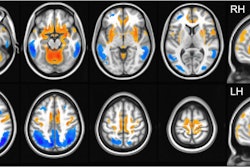

Cerebral F-18 FDG-PET of a 73-year-old man with overlapping features of corticobasal degeneration (CBD) and progressive supranuclear palsy (PSP). The top row shows axial sections at the level of the basal ganglia and mesencephalon of F-18 FDG, CT, and statistical maps. The bottom rows show statistical surface projections with standard deviations from healthy subjects. Note the asymmetry and involvement of the basal ganglia pointing towards CBD and the involvement of mesencephalon and mesial frontal cortex pointing towards PSP. Image and caption courtesy of EJNMMI Research through CC BY 4.0.The group identified 156 patients referred for a brain F-18 FDG PET scans between 2017 and 2019 for suspicion of atypical parkinsonism, with imaging analyzed by a nuclear medicine specialist with more than 10 years of experience in PET neuroimaging. The reference standard for comparison was each patient's follow-up clinical diagnosis.